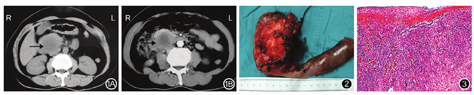

患者女,58岁。因腹上区胀痛10 d于2015年6月30日入院。患者10 d前无明显诱因腹上区胀痛,以腹上区正中为主,间断伴有背部放射痛,无发热,无恶心呕吐,食欲欠佳,大便、小便正常。本次入院体格检查:神志清楚,皮肤、巩膜无黄染,全身浅表淋巴结无肿大;心肺检查正常;腹部平软,右季肋区可触及一大小为6 cm×6 cm的包块,包块边界不清,活动度欠佳,表面有轻压痛,肝脾肋下未扪及。血常规:WBC 8.40×109/L,中性粒细胞占80.6%,Hb 99 g/L,PLT 484×109/L。生化检查:TBil 20.6 μmol/L,DBil 14.30 μmol/L,IBil 6.30 μmol/L,ALT 148.0 U/L,AST 193.0 U/L,GGT 161.0 U/L,ALP 187.0 U/L,LDH 281.0 U/L,血淀粉酶97 U/L。肿瘤标志物:CA19-9 13.59 U/mL,CEA 1.59 ng/mL。B超检查:肝脏囊肿,胆囊轻度炎症改变,胆囊息肉(直径3 mm),胰腺回声欠均匀,胰头部下方见5.0 cm×5.1 cm无回声区,边界不清,内部透声差。CT检查:胰头部囊性占位性病变,大小为4.9 cm×5.0 cm(图1);考虑黏液性囊腺瘤并胰管扩张、胆道梗阻,肝脏多发小囊肿,右肾结石,左肾囊肿。心电图、胸部CT检查均未见异常。术前诊断:胰头占位性病变:胰头囊肿或黏液性囊腺瘤、胰腺恶性肿瘤待查。患者及家属术前均签署手术知情同意书。

患者于2015年7月7日在全身麻醉下行剖腹探查。术中见肝脏大小正常,呈淤胆性改变,腹腔无积液,盆腔未及转移结节,肠系膜根部淋巴结无肿大。胆囊约8 cm×5 cm,未扪及结石,明显肿胀,张力稍高,胆总管扩张,直径约1.5 cm。在胰头部触及一大小7 cm×7 cm肿块,质地中等,呈囊实性改变,边界欠清晰,周围组织明显水肿,未侵犯肠系膜上动静脉。行保留幽门的胰十二指肠切除术,手术过程顺利,手术时间8 h,术中出血量为400 mL。切除的病变大体标本见图2,沿胰腺纵轴切开胰腺,肿块直径为7 cm,囊性,壁厚,内壁呈炎性改变,有较多坏死组织,囊液呈黄白色脓性改变。术后病理学检查:胰头脓肿(图3),淋巴结慢性炎;十二指肠亚急性炎;慢性胆囊炎。术后复查引流液淀粉酶均正常,第16天出院。术后3个月复查腹部CT,未见明显异常。